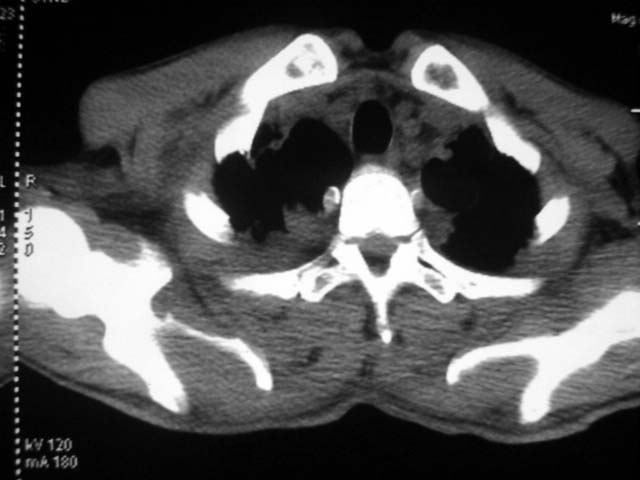

男,52岁,发热2月,糖尿病史。

抗结核治疗irpz方案,血糖未治疗,空腹15.9左右。症状无好转,左胸痛。

复查ct

2、双肺见多发片状及结节状高密度影,大多数病灶中心均见“空泡征”。

3、纵隔内淋巴结肿大。

结果:两肺继发性肺结核并曲霉菌感染。